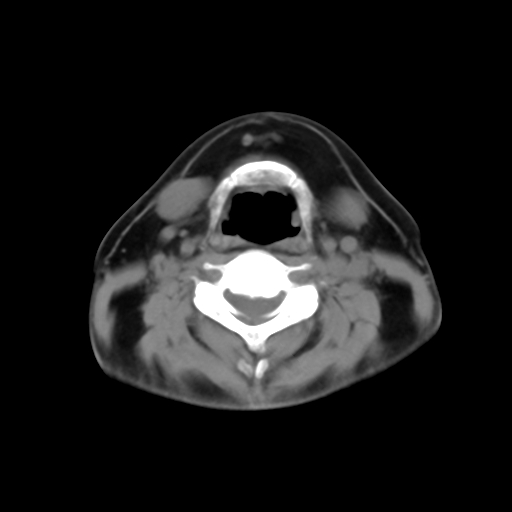

标题: CT24019:男,45岁,发现颈部肿物5个月。 [打印本页]

标题: CT24019:男,45岁,发现颈部肿物5个月。

男,45岁,发现颈部肿物5个月,彩超示:双侧颈部及下颌部软组织增厚。

考虑双侧颈项部良性对称性脂肪增多症。